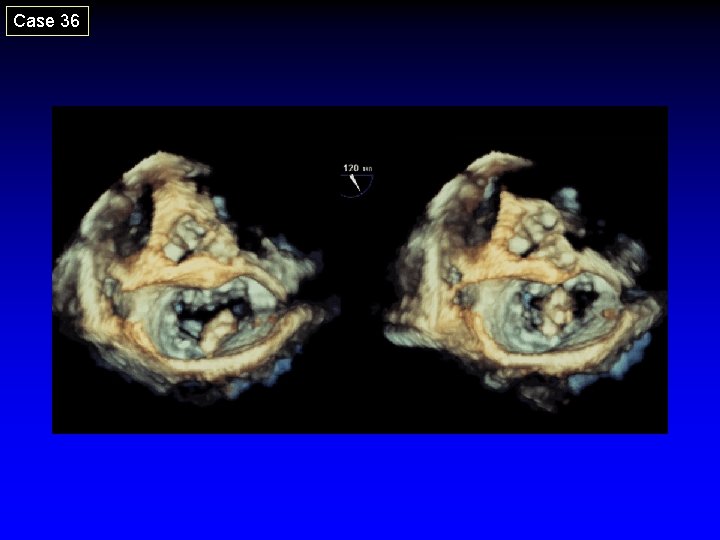

Case 36

7. Post-Clip Placement Assessment Echo Guidance • Degeree of MR • Diastolic transmitral gradient • Achievement of double orifice Then, close the clip incrementally under echo-guidance